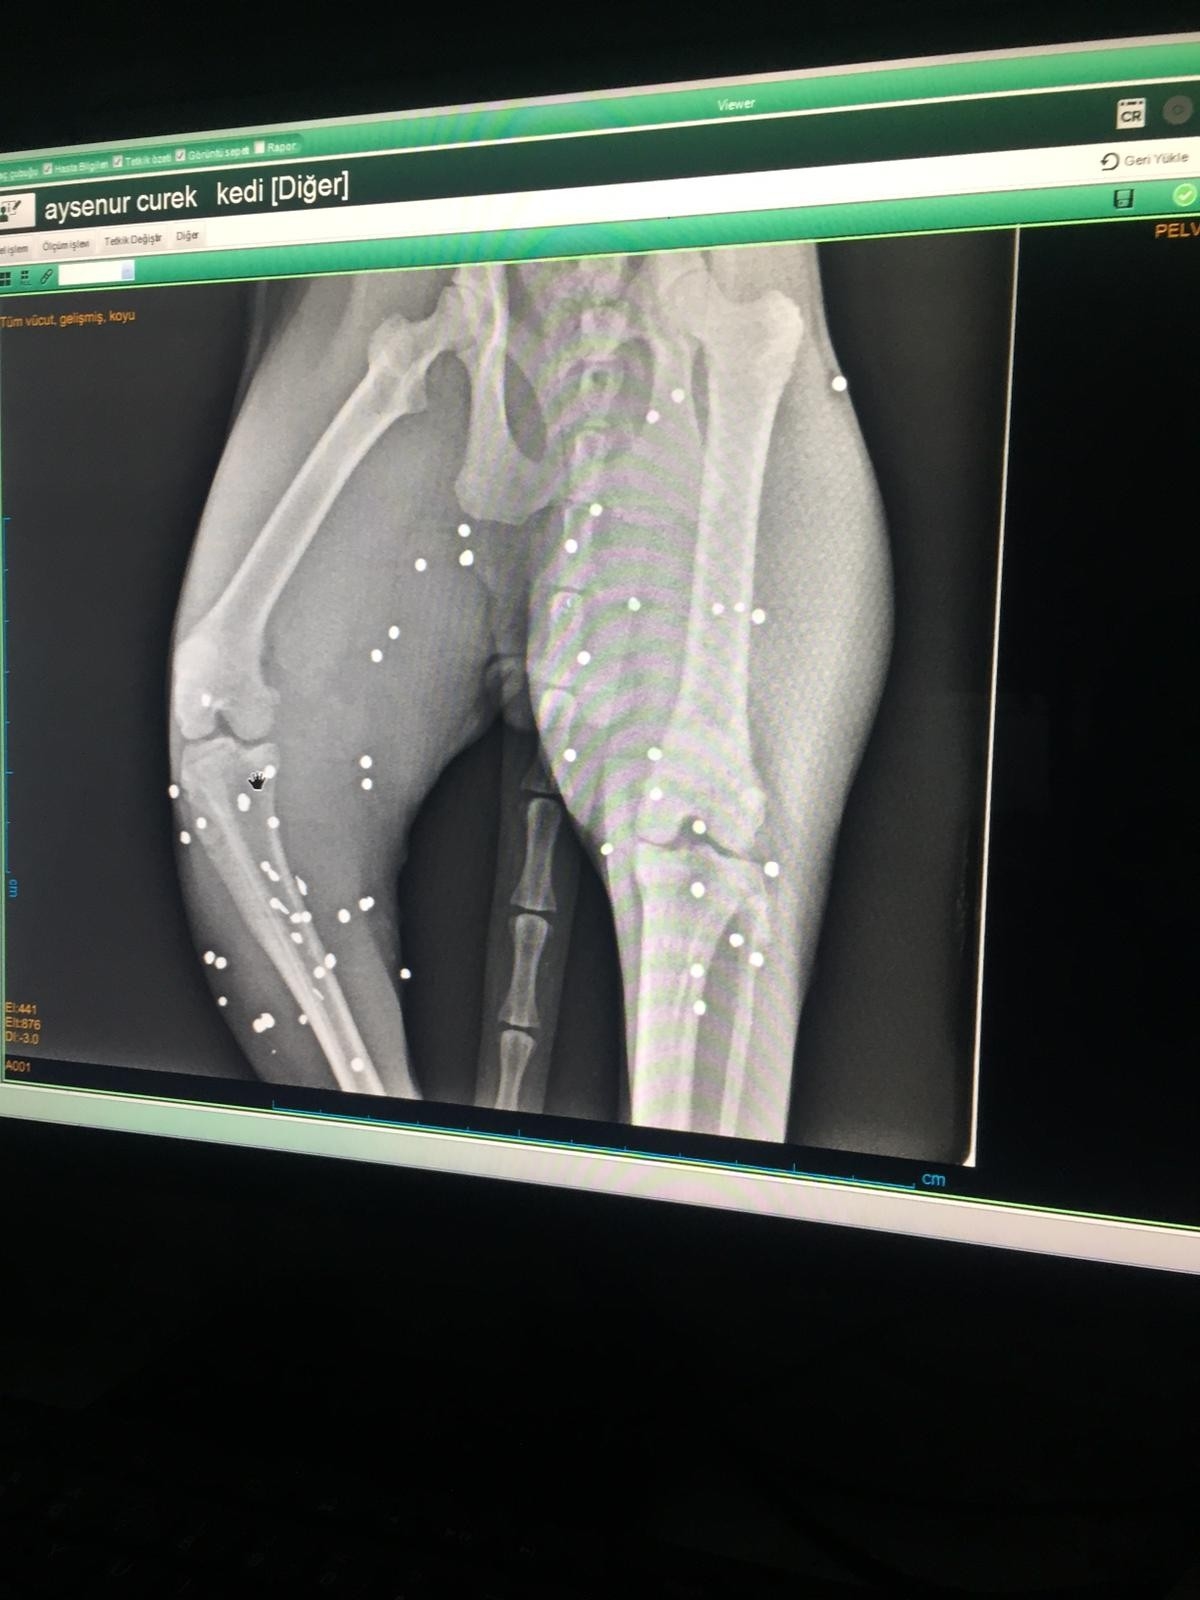

Eve gelerek kediyi alıp kliniğe götüren veteriner tarafından filmleri çekilen kedinin vücudunun arka ayaklarının olduğu bölgede tüfekle ateş edilmesine bağlı çok sayıda saçma izine rastlandı. Güçlükle yürüyen ve arka ayaklarının üzerine güçlükle basan kedinin tedavisine başlanırken, Manavgat İlçe Jandarma Komutanlığı ekipleri tarafından olayla ilgili inceleme başlatıldı.

Veteriner Hekim Atila Sargın, Şenay Yılmaz’ın kendisini aramasından sonra olaydan haberdar olduğunu belirterek, "Gelip baktığımda kedinin durumunun kötü olduğunu gördüm. Hemen aldım kliniğe götürdüm. Röntgeni çekince gördüm ki kedinin arka tarafında çok sayıda saçma var. Yani kedinin arka tarafında tüfekle ateş edilmiş” dedi.